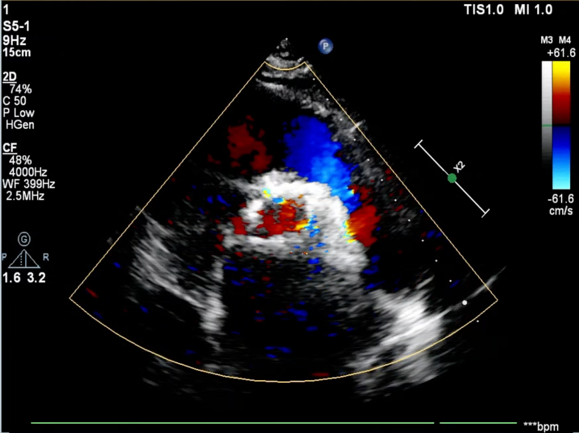

TaurusNXT植入过程

手术采用22 mm TaurusAtlas球囊进行预扩,植入AV23TaurusNXT主动脉瓣。第一次释放后位置偏高,瓣膜完全回收。第二次释放到工作位,检测左右冠血流灌注情况,考虑左瓣叶的瓣尖钙化影响左冠脉血流,使用第二次回收后,预置LCA保护。之后再次释放瓣膜至工作位,在GuidezillaII支撑保护下送 4.0×18mm 支架至 LAD 近段,之后瓣膜精准释放,后用22mm TaurusAtlas球囊后扩。术后即刻经胸超声心动图评估显示少量瓣周漏,平均跨瓣压差为10mmHg,主动脉瓣口峰值流速为2.3m/s,有效瓣口面积为1.80cm²,血流动力学指标理想。

血流动力学改善,瓣膜形态良好,少量瓣周漏